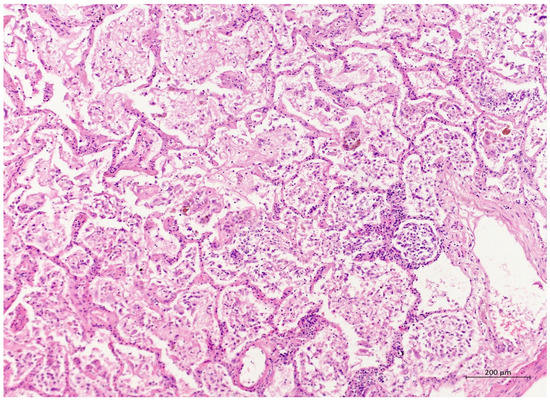

Figure 2. (H&E, 10×) H&E staining showing lung parenchyma with alveoli filled with exudated foamy fluid, hyaline membrane remnants, numerous desquamated cells, and mixed inflammatory infiltrate. The proliferation of myofibroblasts can be seen sporadically. The interalveolar septa were somewhat thickened.

A 60 year old male smoker with a history of arterial hypertension and myocardial infarction developed typical COVID-19 symptoms in April 2021—cough, exertional dyspnoea, chest tightness, and fever. Developing prior to the widespread availability of antiCOVID-19 vaccines, he was unvaccinated. Four days after the onset of symptoms, he was admitted to the Pulmonary Department of the University Hospital Brno due to the worsening dyspnoea. He tested positive for SARS-CoV-2. The exact viral variant was not identified. The predominant variant in the Czech population was B.1.1.7 (Alpha) at that time. His initial chest X-ray revealed diffuse lung infiltrates, especially in the right upper-middle quadrant. Despite receiving standard treatment with remdesivir for five days, corticosteroids (methylprednisolone 80 mg intravenously per day), and a prophylactic dose of low-molecular-weight heparin (LMWH), his dyspnoea worsened. Hence, supplemental oxygen and antibiotics (i.e., clarithromycin 500 mg IV BID and ceftriaxone 2 g IV BID for 5 days) were administered. Due to the progressively increasing levels of D-Dimers in laboratory tests, CT angiography was performed, showing typical findings consistent with COVID-19 pneumonia of diffuse lung parenchyma involvement without any signs of pulmonary embolism (Figure 1). The patient’s oxygen was gradually increased to achieve a peripheral blood saturation of >90%. On day 11, the patient was transferred to the ICU after his saturation dropped to 50–60% despite an oxygen flow via face mask of approximately 15 litres per minute. High-flow oxygen therapy (HFOT) with awake prone positioning was commenced, and corticosteroids were switched from methylprednisolone 80 mg to dexamethasone 6 mg IV per day. Despite ten days of corticosteroid administration, the patient’s clinical condition began to deteriorate significantly, and his hypoxaemia worsened. On day 12, he was intubated and placed on invasive ventilation with aggressive parameters (positive end-expiratory pressure: 12 cm H2O; fraction of oxygen: 80%). Bronchoalveolar lavage (BAL) was performed with the PCR testing showing more than 2 million copies of SARS-CoV-2 per millilitre (a significant number); no fungal DNA was detected at this time. As the patient became anuric, daily dialysis treatment commenced on day 13. Ventilator-associated pneumonia (VAP) caused by Klebsiella pneumoniae producing extended-spectrum beta-lactamase (ESBL) was confirmed by BAL fluid cultivation, and meropenem 2 g per day in continuous infusion was started. Serum levels of cardiac markers were elevated (troponin T: 67 ng/L; NT pro Brain Natriuretic Peptide (NTproBNP): 3892 ng/L), indicating advancing myocardial injury. Norepinephrine infusion was needed to achieve adequate blood pressure. The capillary refill time was prolonged over 2 s, consistent with circulatory dysfunction. A day later, the patient developed atrial fibrillation and hemodynamic instability with doses of norepinephrine up to 0.5 µg/kg/min. On day 16, a tracheostomy was performed, while the ventilation remained fully controlled with a P/F (PaO2/inspiration fraction of O2) index below 150. Two days later, the progression of circulatory dysfunction became apparent, accompanied by an elevation of inflammatory markers. Follow-up BAL was performed, empirical vancomycin was added on day 19, and doses were adjusted respecting dialysis procedures. Abdominal ultrasound revealed no clear site of a new infection. Blood cultures were negative, and BAL showed more than 3 million copies of SARS-CoV-2 and 1200 copies of Cryptococcus neoformans per millilitre/BAL. Serum panfungal antigen ((1,3)-β-glucan D) and serum cryptococcal antigen (i.e., glucuronoxylomannan) levels were negative. Over the next four days, organ dysfunction slightly improved; therefore, the patient was slowly weaned-off sedation, and the mode of ventilation was switched to pressure support. On day 21, vancomycin was switched to linezolid 600 mg IV BID. On day 22, a follow-up BAL was performed. PCR showed borderline positivity for Cryptococcus neoformans (300 copies per millilitre), and serum positivity for cryptococcal antigen was detected. Combined antifungal therapy with liposomal amphotericin B (Abelcet) 500 mg IV per day and fluconazole 800 mg IV per day was commenced. Blood cultures were negative for bacteria and fungi. Cerebrospinal fluid analysis, including PCR, ruled out CNS dissemination. On day 24, the patient’s circulatory instability progressed rapidly with no response to vasopressors and inotropes, which led to a subsequent cardiac arrest followed by unsuccessful cardiopulmonary resuscitation (CPR). Multiorgan dysfunction caused by COVID-19 infection and cryptococcal pneumonia was stated as the primary cause of death from a clinician’s perspective. The most significant feature during the histopathological examination was the severe diffuse alveolar damage (DAD) (Figure 2), specifically its exudative/proliferative stage, due to the prolonged period of COVID-19 pneumonia. In addition, a considerable number of dispersed intra-alveolar microorganisms, with a thick mucus capsule, were found in the lung parenchyma (Figure 3). These microorganisms (variably sized: approximately 7–20 μm) stained with both Alcian blue (Figure 4) and Giemsa (Figure 5). There was only a very subtle inflammatory reaction in the surrounding tissue, mostly lymphocytic. A post-mortem lung smear was microbiologically tested and returned positive for Cryptococcus neoformans. Thus, we consider secondary lung cryptococcosis as proven. Respiratory failure as a result of DAD was the immediate cause of death of the patient.